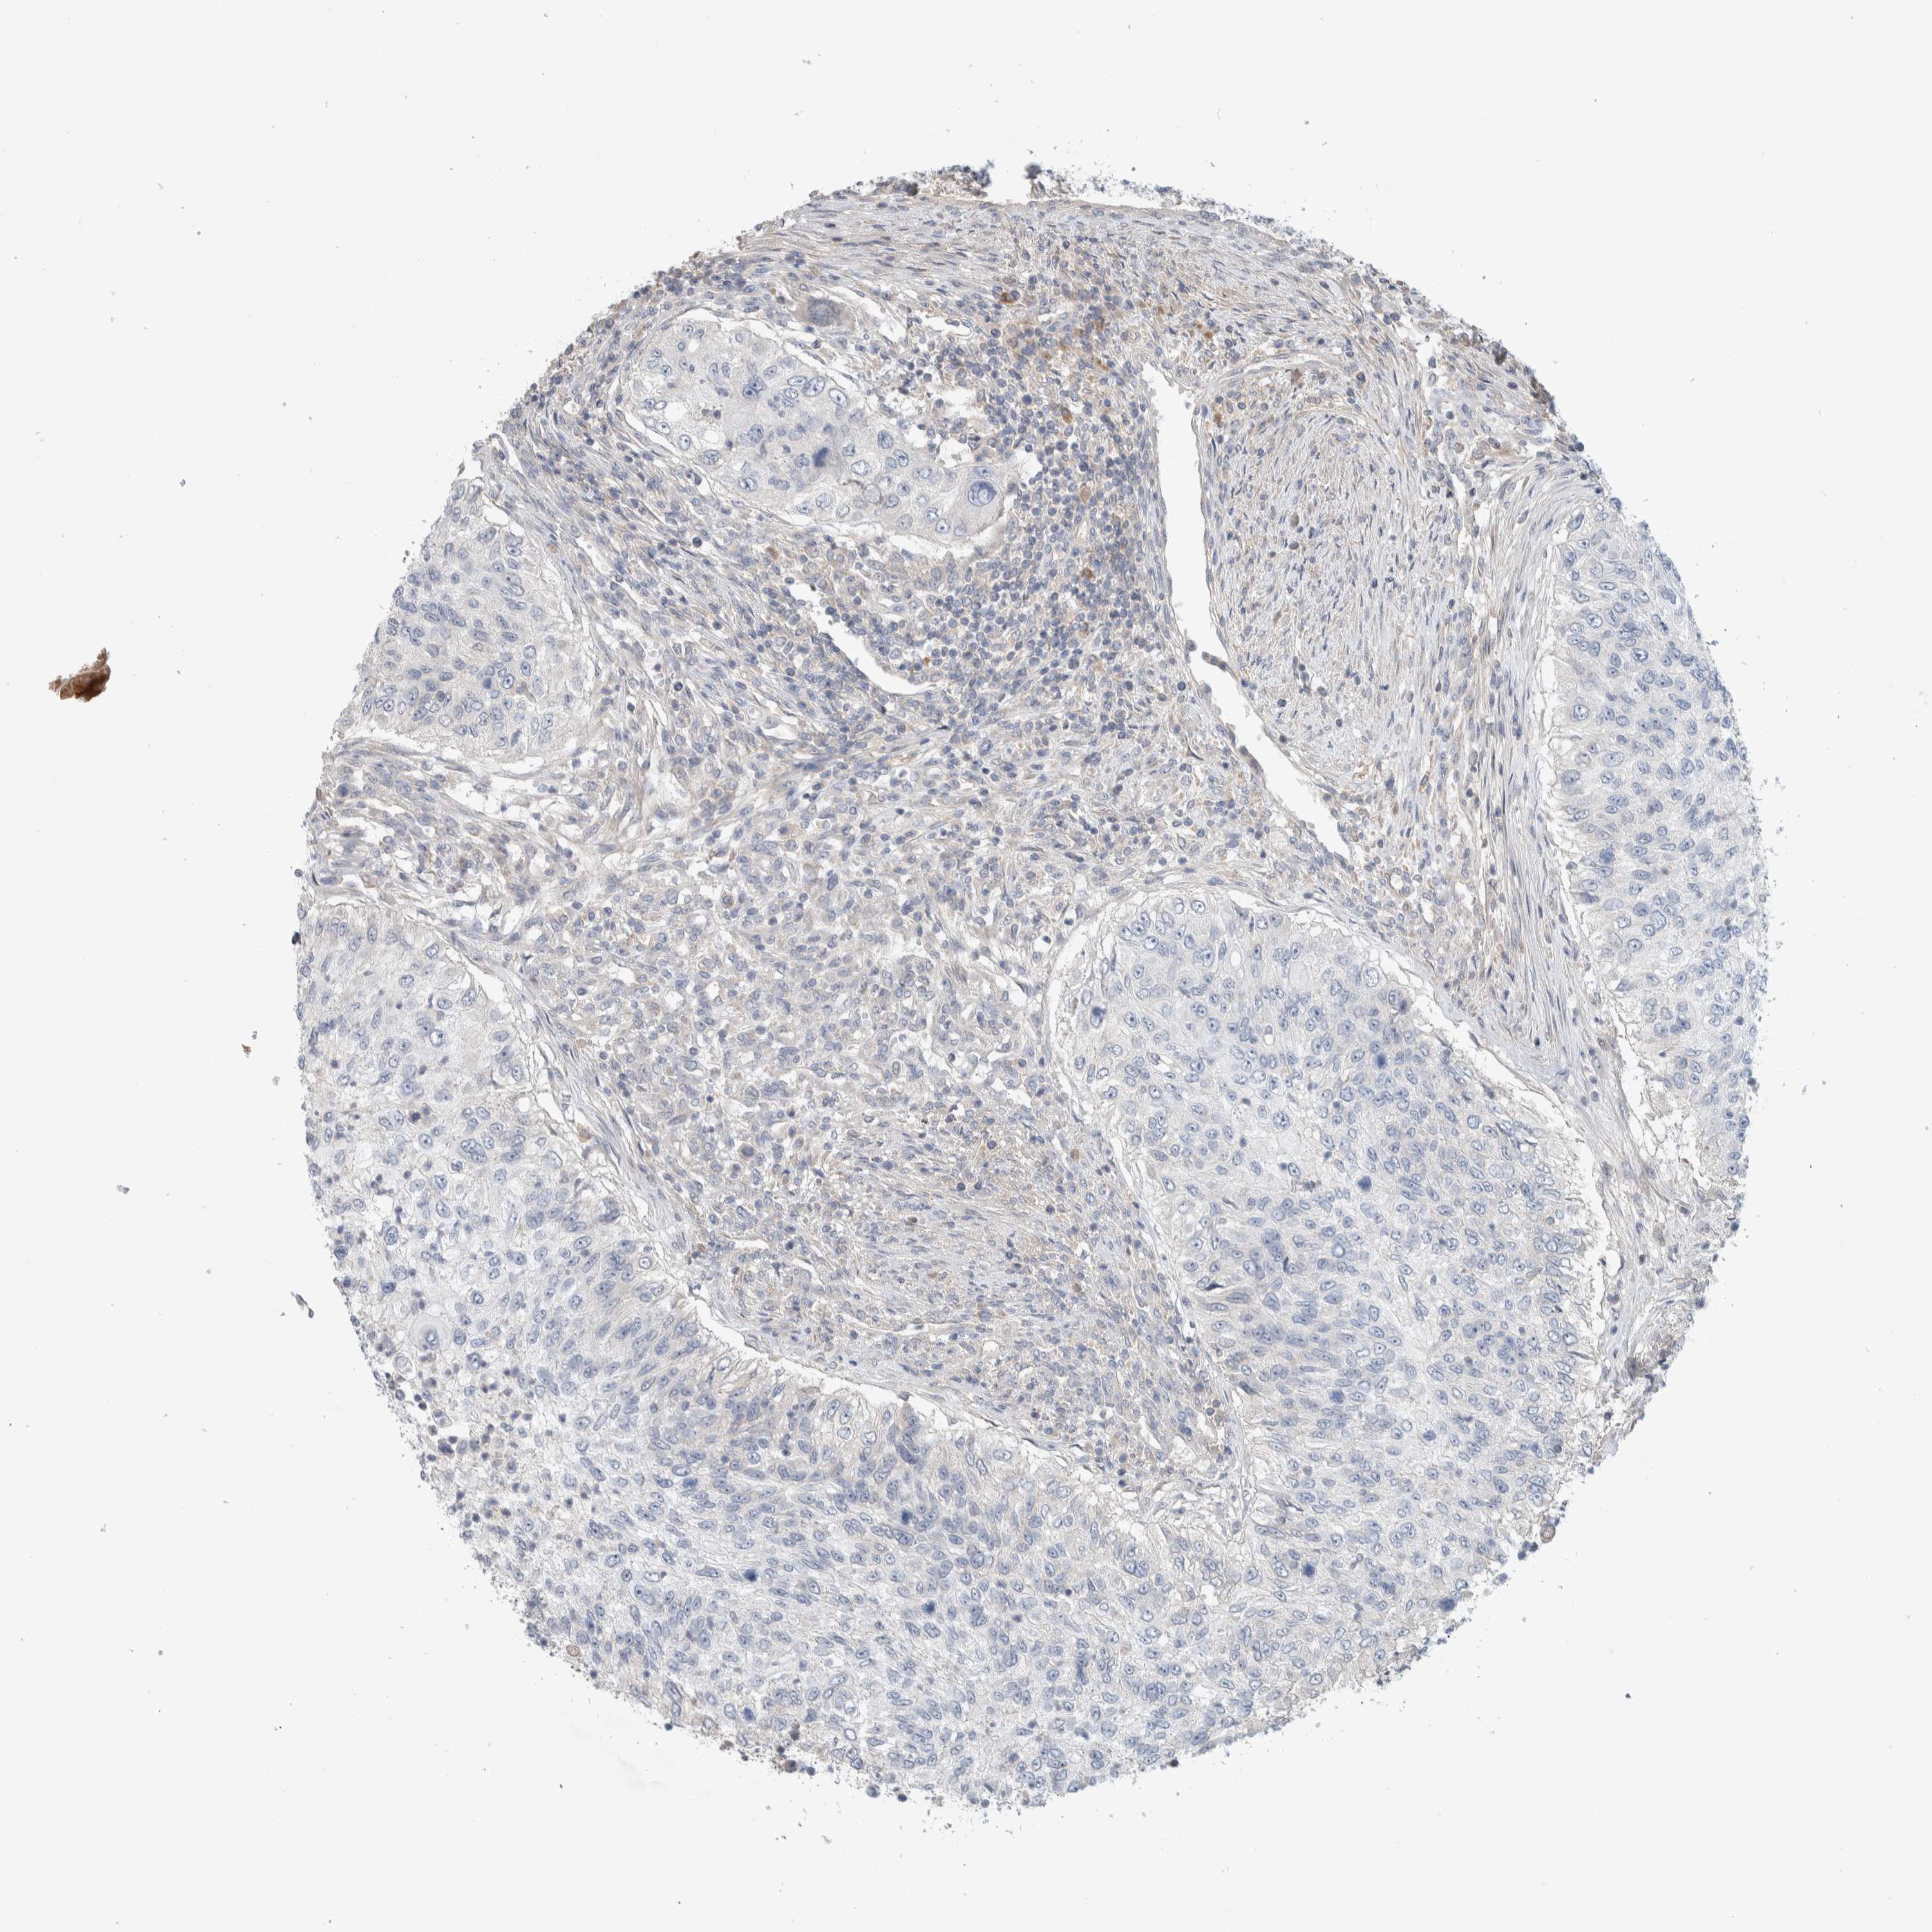

UROTHELIAL CANCER - Protein expressioni

A mouse-over function shows sample information and annotation data. Click on an image to view it in a full screen mode. Samples can be filtered based on level of antibody staining by selecting one or several of the following categories: high, medium, low and not detected. The assay and annotation is described here.

Note that samples used for immunohistochemistry by the Human Protein Atlas do not correspond to samples in the TCGA dataset.

Antibody stainingi

Antibody staining in the annotated cell types in the current human tissue is reported as not detected, low, medium, or high, based on conventional immunohistochemistry profiling in selected tissues. This score is based on the combination of the staining intensity and fraction of stained cells.

Each image is clickable and will lead to virtual microscopy that enables deeper exploration of all samples and also displays staining intensity scores, fraction scores and subcellular localization as well as patient and tissue information for each sample.

Antibody HPA023938

Antibody HPA023945

Antibody HPA024011

Antibody CAB020841

Staining

High

Medium

Low

Not detected

Intensity

Strong

Moderate

Weak

Negative

Quantity

>75%

75%-25%

<25%

None

Location

Nuclear

Cytoplasmic/membranous

Cytoplasmic/membranous,nuclear

Urothelial carcinoma, Low grade

Urothelial carcinoma, High grade